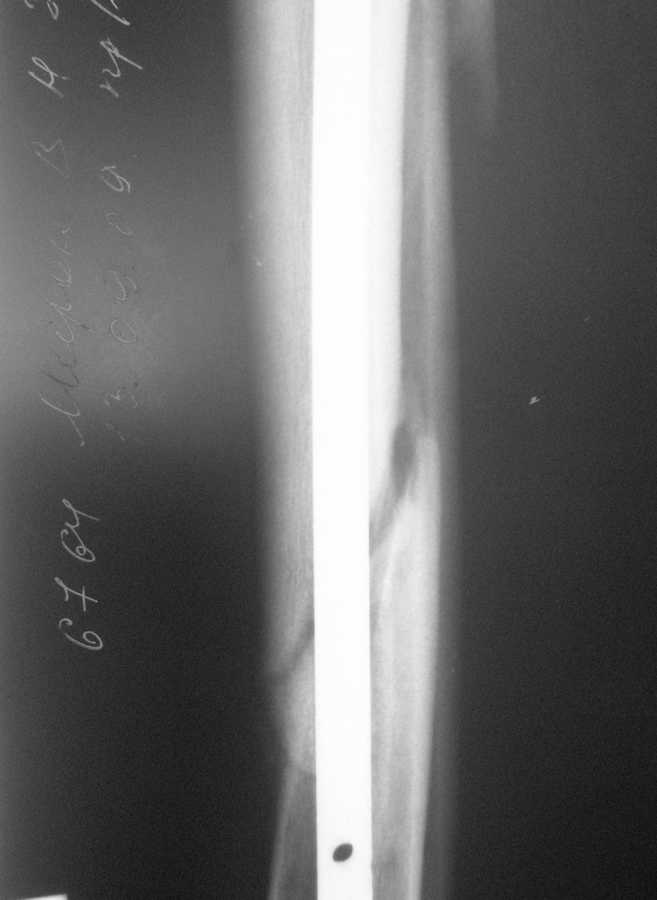

БИОС голени. В чем ошибка? |

В январе 2009 года нами оперирована пациентка с переломом н\3 голени штифтом Expert. Динамизация через 4 месяца, пациентка при этом уже ходила с тростью. Дома периодически передвигалась без дополнительной опоры.

В настоящее время - через 9 месяцев с момента операции периодически в вечернее время беспокоят ноющие боли в места перелома (не постоянно). При беседе выяснено, что боли чаще беспокоят после того, как днем она походит по дому без трости. Пальпаторно по гребню берцовой кости болей нет, но по задне-внутренней поверхности б\б кости пальпирутеся западение на уровне места перелома.